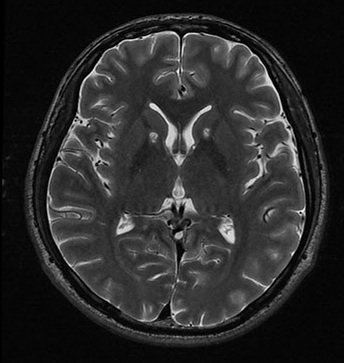

뇌 MRI + MRA

뇌경색, 뇌졸증, 뇌종양, 뇌출혈 등 뇌에 발생할 수 있는 질병을 미리 찾아 낼 수 있는 검사입니다.

뇌 MRI

뇌의 구조나 조직을 보고 이를 통해 병을 진단하는 검사입니다.

MRI 방식이기 때문에 방사선 피폭이 없었다는 장점이 있습니다. 환자는 누워만 있으면 기기가 잉동하여 뇌의 구조를 촬영해 줍니다. 가격이 비싸다는 단점이 있습니다.

구조만 보기 때문에 이 보다는 뒤에 나올 MRA를 추천드립니다.

뇌 MRA (추천)

자기공명 혈관영상(Magnetic Resonance Angiography)을 뜻하며, 직이는 혈액을 조사하므로 특정 부위의 혈관을 영상화하는 기법입니다. 이를 통해 뇌의 혈관 상황등을 확인할 수 있고, 특히 뇌혈관의 꽈리와 같이 평소엔 이상이 없다가 혈압상승 등과 같은 이상 상태에 발생할 수 있는 뇌출혈과 이로 인해 유발될 수 있는 중풍과 같은 질병을 미리 진단할 수 있다는 점에서 효용성이 좋은 검사입니다.

뇌혈관의 질병은 사전에 미리 인지하기도 어렵고, 발생할 경우 치명적이기 때문에 해당 검사를 하시는 걸 추천드립니다.